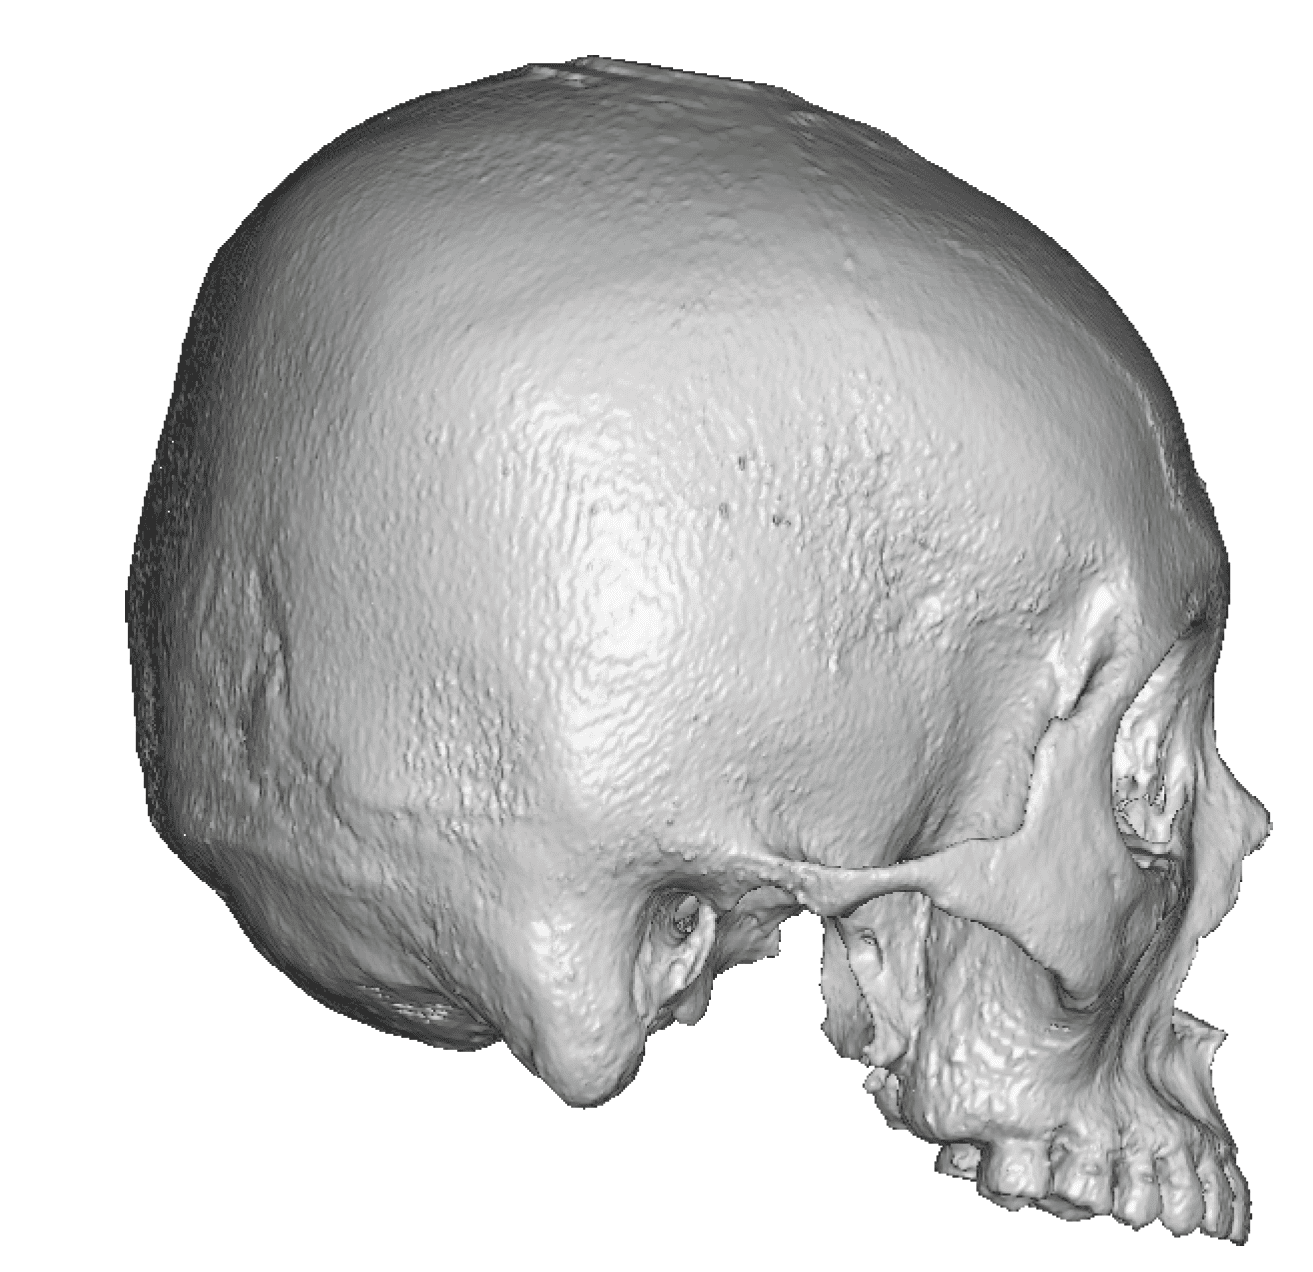

Patient 70

Adult with untreated sagittal craniosynostosis head shape.

Scaphocephalic skull reshaping with occipital and sagittal bone reductions with placement of custom skull implant.

Adult with untreated sagittal craniosynostosis head shape.

Scaphocephalic skull reshaping with occipital and sagittal bone reductions with placement of custom skull implant.